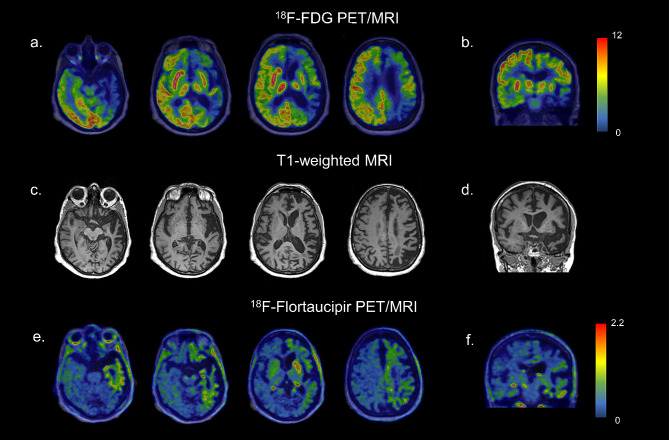

Neuropsychological tests indicated multi-domain amnestic mild cognitive impairment (aMCI), and neurological examination revealed asymmetrical involuntary hyperkinetic movements. Imaging studies showed severe left-sided atrophy and hypometabolism in the left frontal and temporoparietal cortex. [18F]Flortaucipir PET exhibited moderately increased tracer uptake in hypometabolic areas. The diagnosis initially considered Alzheimer’s disease (AD), frontotemporal degeneration (FTD), and corticobasal degeneration (CBD), cerebral hemiatrophy syndrome, but imaging and cerebrospinal fluid analysis excluded AD and suggested fused-in-sarcoma-associated FTD (FTLD-FUS), a subtype of the behavioural variant of FTD.

[18F]FDG PET of the brain showed severe asymmetric hypometabolism in the left frontal and temporoparietal cortex, the left caudate nucleus, and, to a lesser extent, in the left putamen (Fig. 1a, b).

The patient underwent also a [18F]Flortaucipir tau PET study in the context of a research project of the memory clinic of Geneva University Hospitals. The visual assessment of the tau PET scan revealed an increased tracer uptake in areas characterized by hypometabolism as described before. Specifically, a weak neocortical uptake was found in the left frontal, parietal, temporal, and insular cortices, associated with a more intense uptake in the left caudate nucleus (Fig. 1e, f). According to current U.S. Food and Drug Administration statement, the increased tracer uptake in those areas was considered nonsignificant for AD, since neocortical uptake in the left frontal, parietal, temporal, and insular cortices did not reach a signal of more than 65% above the cerebellar mean. In the context of diffuse off-target binding, we found an asymmetric and moderate uptake in the left caudate nucleus, exceeding 65% of the cerebellar mean. No abnormalities were observed in the right hemisphere (Fig. 1e, f).

Taking together the clinical picture and imaging exams allowed the hypothetical diagnosis of a neurodegenerative condition, namely a subtype of the bvFTD, called FTLD-FUS with some features of CBS. On the one hand, the clinical evaluation revealed markedly asymmetric choreiform involuntary movements and, on the other hand, neuroimaging results showed the severe left hemisphere atrophy, the left frontotemporoparietal cortex and the left caudate nucleus hypometabolism on [18F]FDG PET and the non-AD [18F]Flortaucipir tau PET pattern with an asymmetric and moderate uptake in the left caudate nucleus.

Few neuroimaging studies assessed the in vivo molecular pathology and neurodegeneration in these cases due to the rarity of the pathology-proven cases during lifetime. Soleimani-Meigooni and coworkers [ref. 5] previously described tau uptake assessed by PET in a patient with a pathological diagnosis of FTLD-FUS, revealing intense uptake in the left caudate. Our reported case resembles this aforementioned tracer uptake, and also minimal tracer retention corresponding to areas of significant atrophy (Fig. 1e, f). The hypometabolism pattern described in our case adds molecular information to previous works about this rare entity.